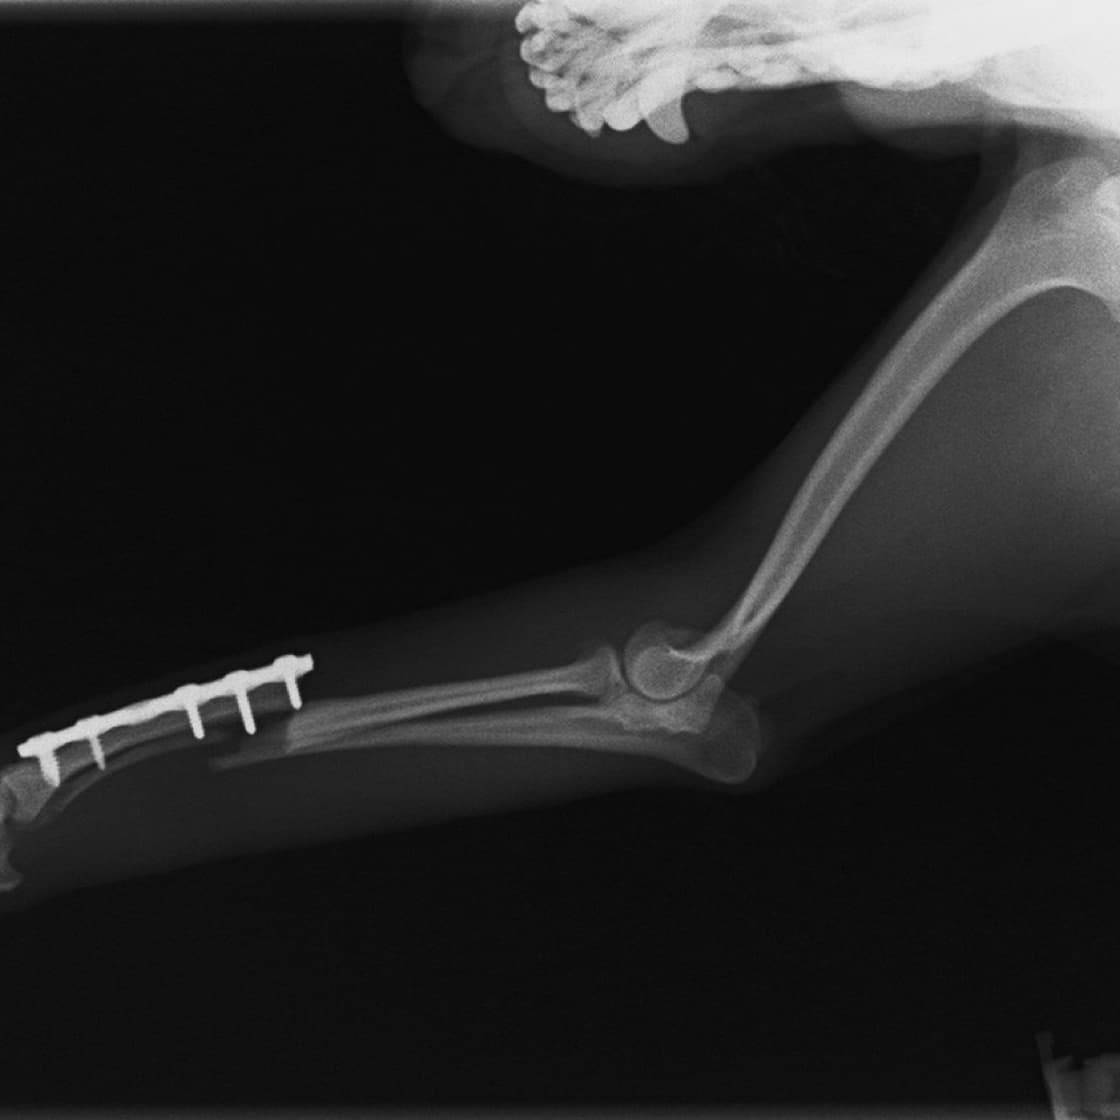

トイプードル 右遠位橈尺骨短斜骨折のALPSによる内固定